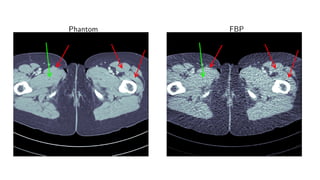

Results

human data

Results for ray transform inversion in 2D.

Inverse problem:

g = P(f ) + δg

Geometry: fan beam 1000 angles

Noise: Poisson noise (low dose CT)

Data: 512 × 512 pixel human data

Compare to:

FBP

Total Variation

Post-processing deep learning by U-Net

Phantom FBP

Phantom TV

Phantom Learned U-Net

Phantom Learned Primal-Dual

Quantitative

Method PSNR (dB) SSIM Runtime (ms) Parameters

FBP 33.65 0.829 423 1

TV 37.48 0.946 64 371 1

Learned U-Net 41.92 0.941 463 107

Learned Primal-Dual 44.11 0.969 620 2.4 · 105